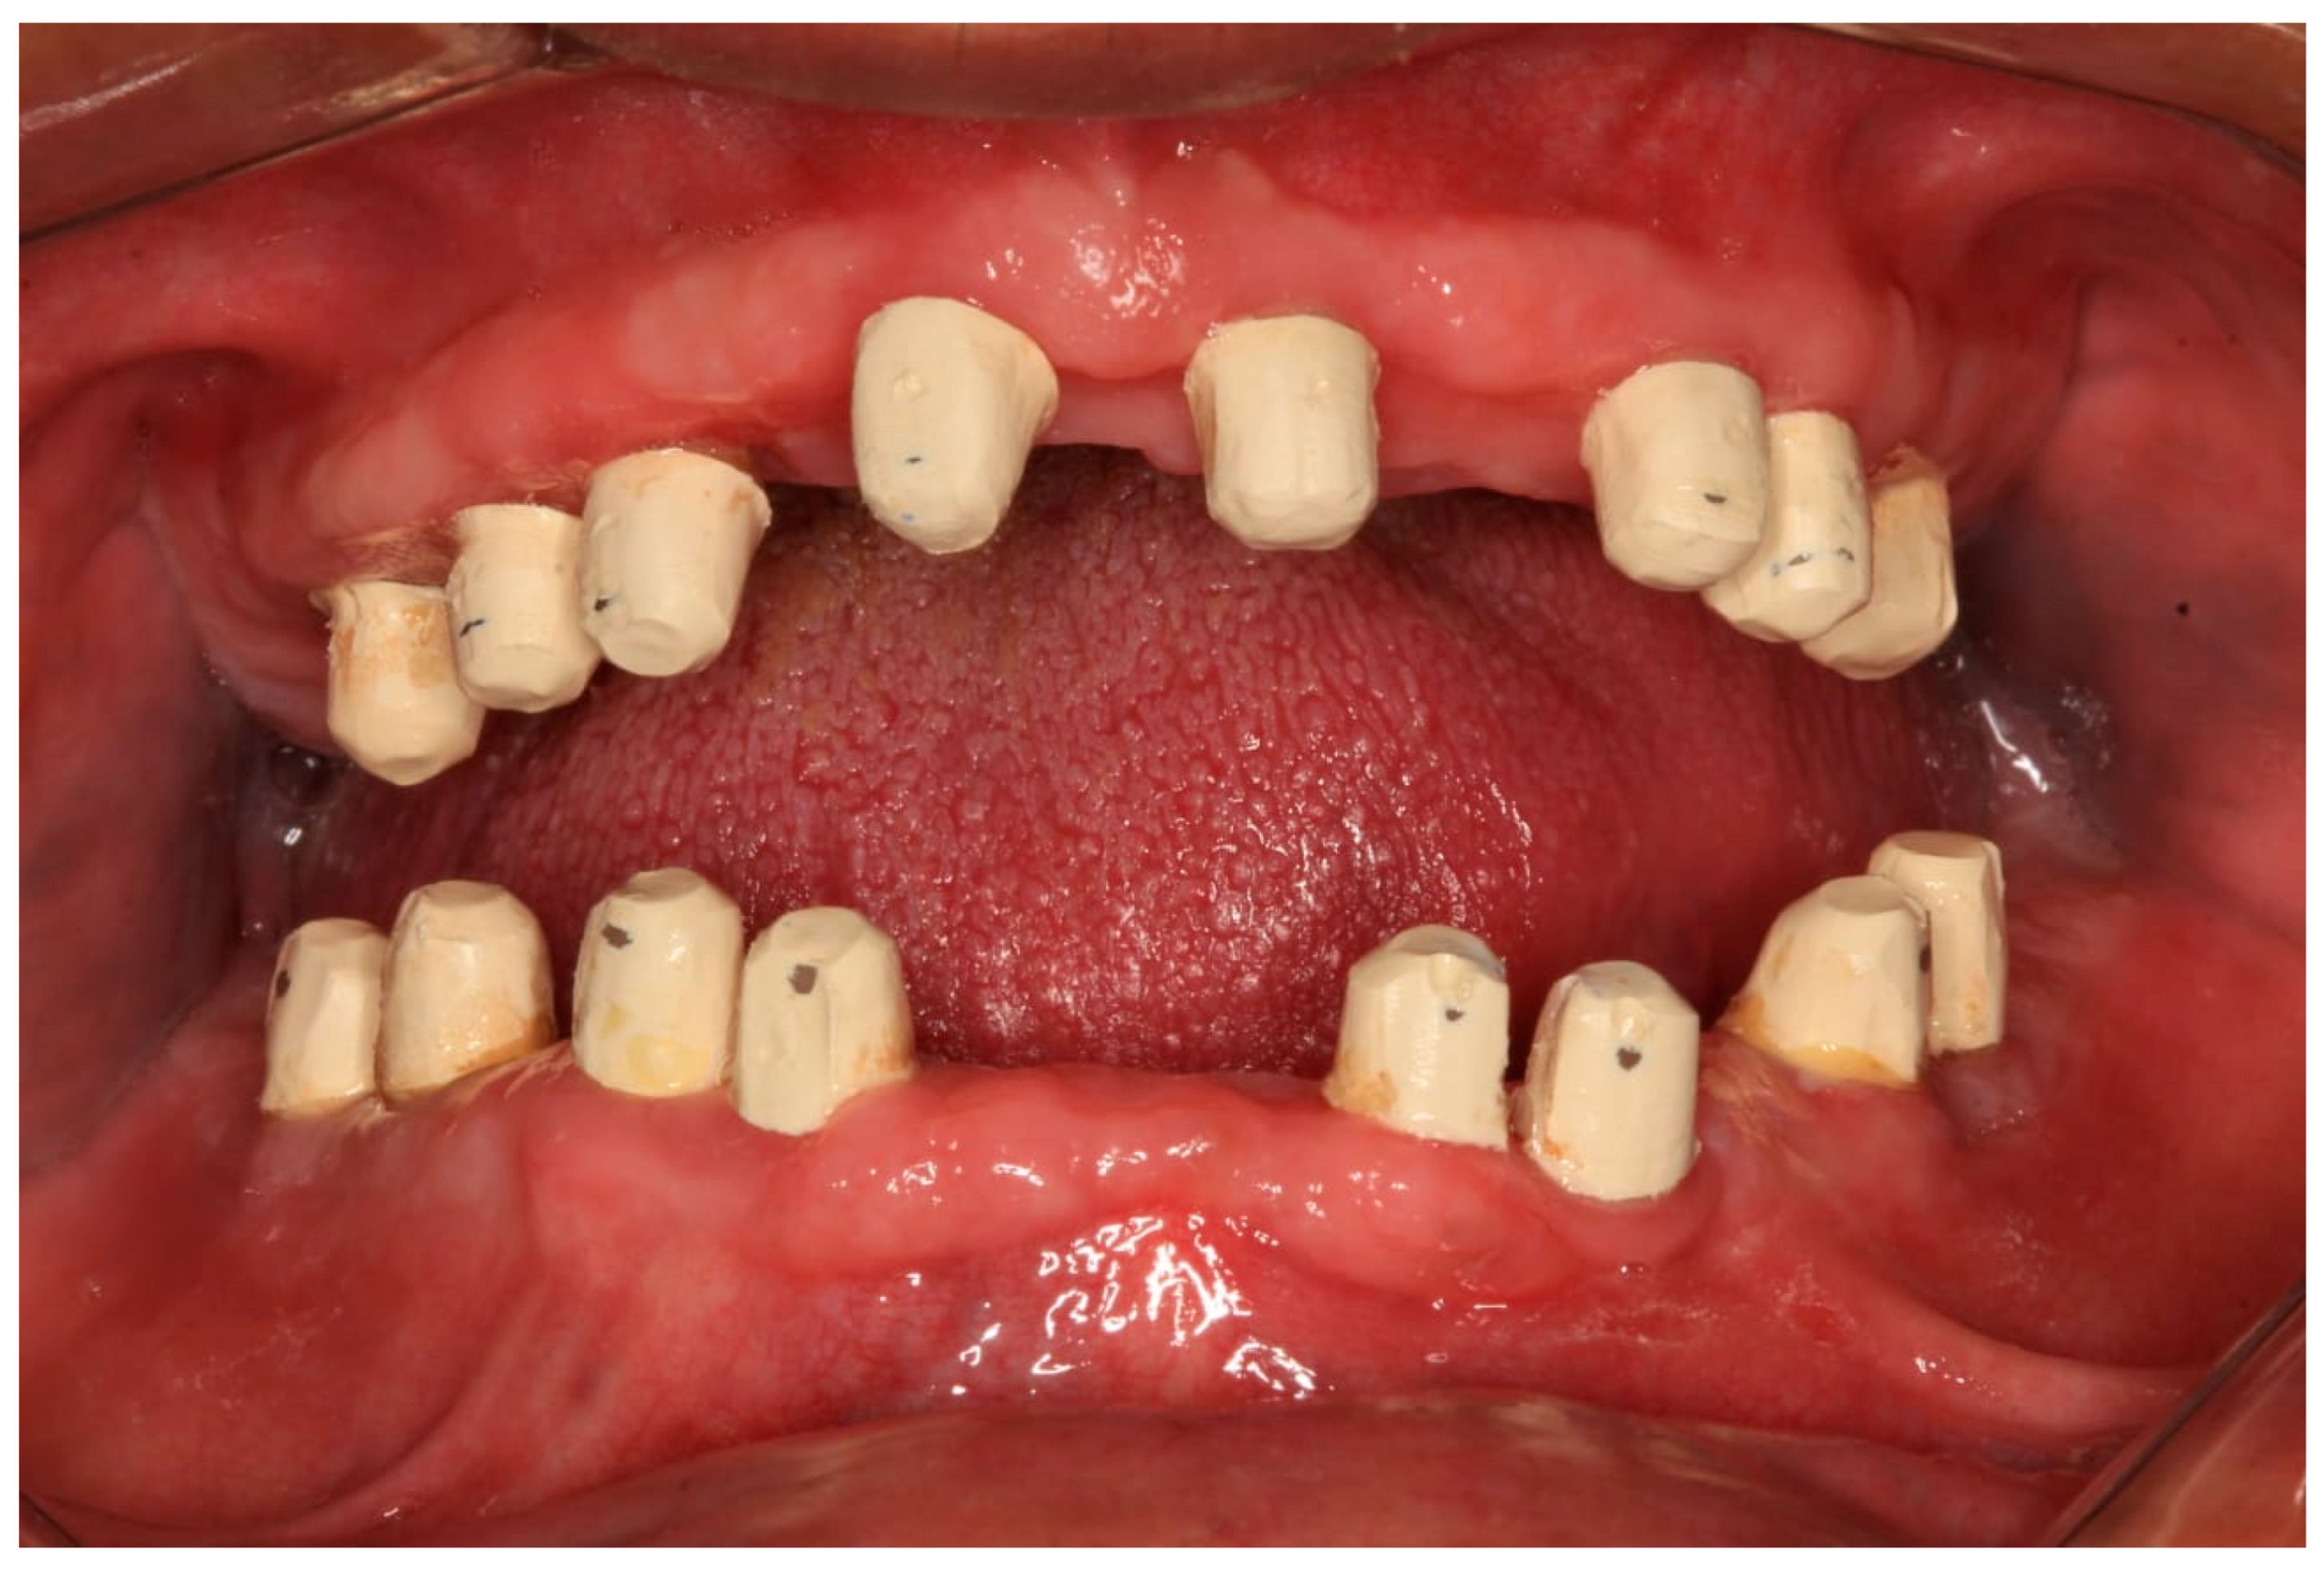

The clinical dental assessment, at the time, indicated a completely edentulous maxilla and a partially edentulous mandible. The residual mandibular teeth exhibited periodontal compromise, classified as Grade 3 mobility according to the Miller Classification, with multiple cavities and a poor overall prognosis (Figure 1).

Figure 1. Preoperative oral condition. (A) The edentulous maxilla. (B) Partially edentulous mandible. (C) Maxillary denture and mandibular partial denture.